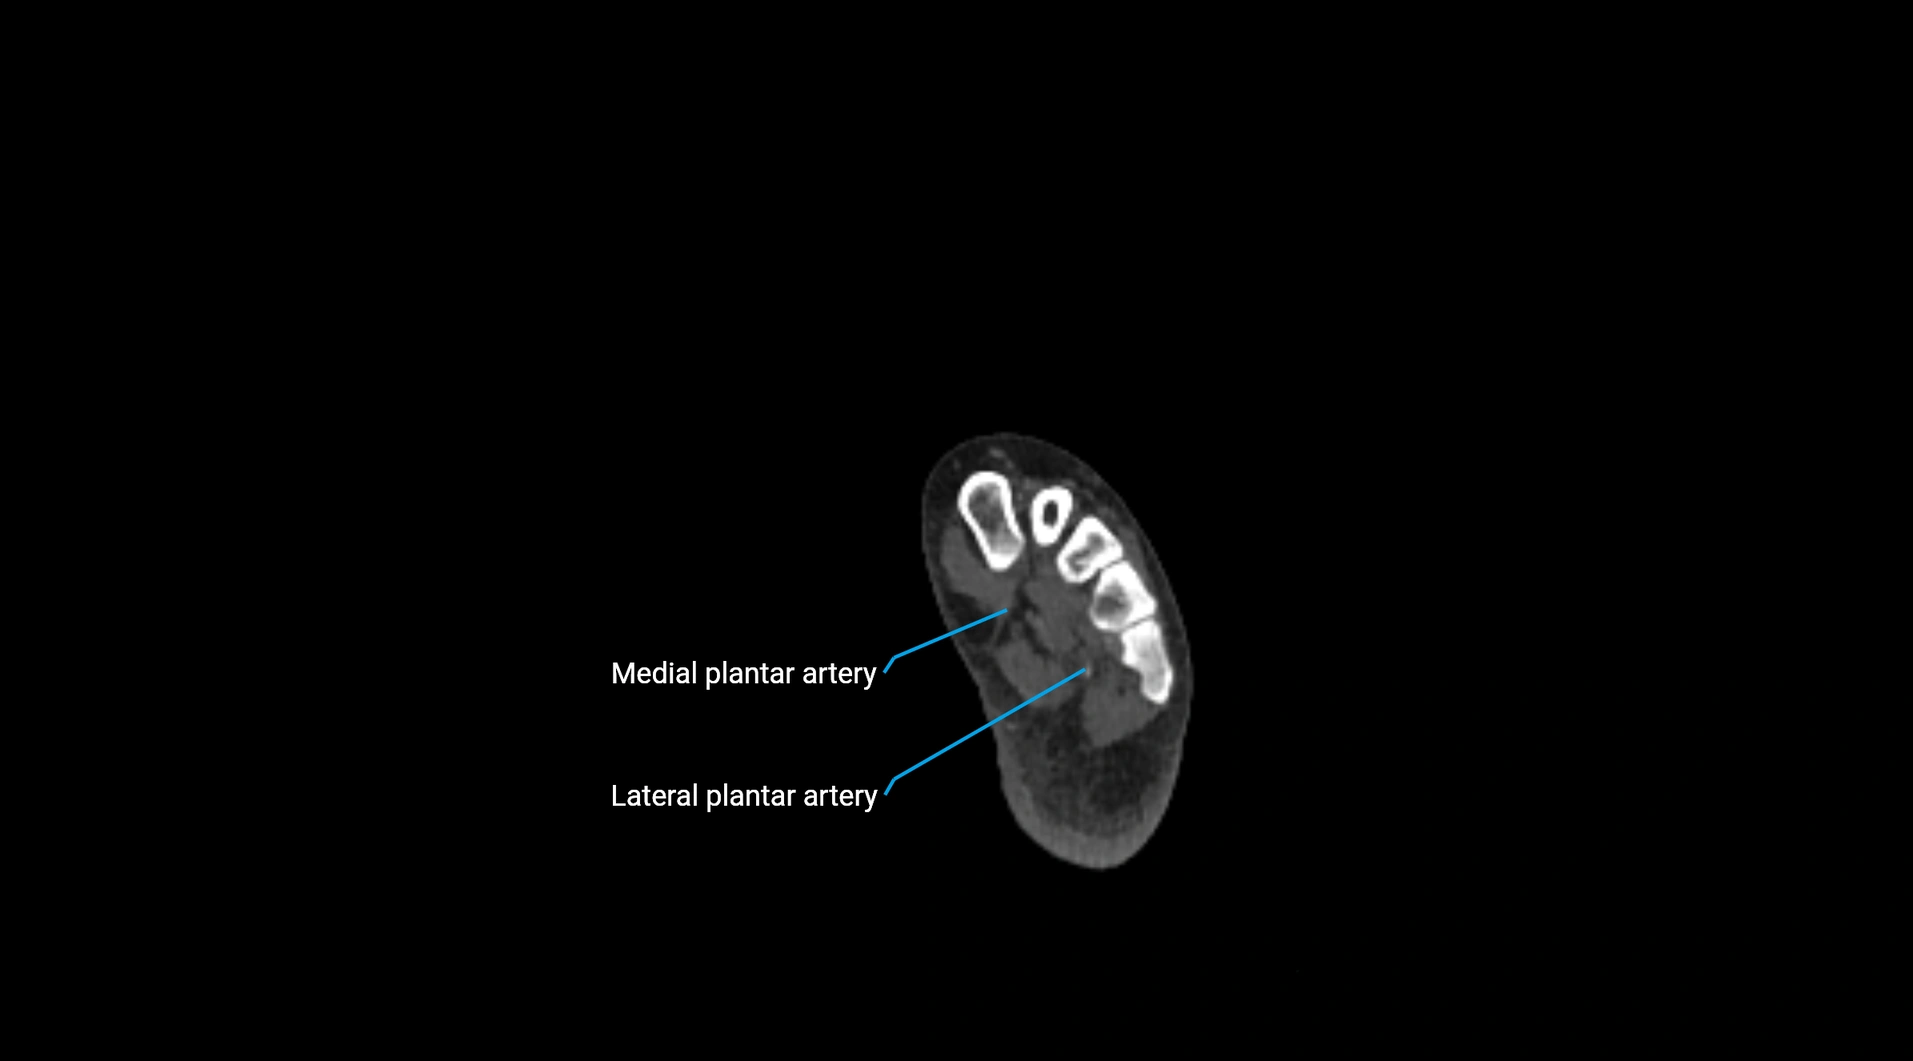

CT images

image

Contrast-enhanced CT (CTA):

• Gold standard for abdominal aortic imaging

• Provides excellent detail of lumen, wall, aneurysm, thrombus, and branch vessels

• Multiplanar and 3D reconstructions help in aneurysm measurement, stent graft planning, and dissection evaluation